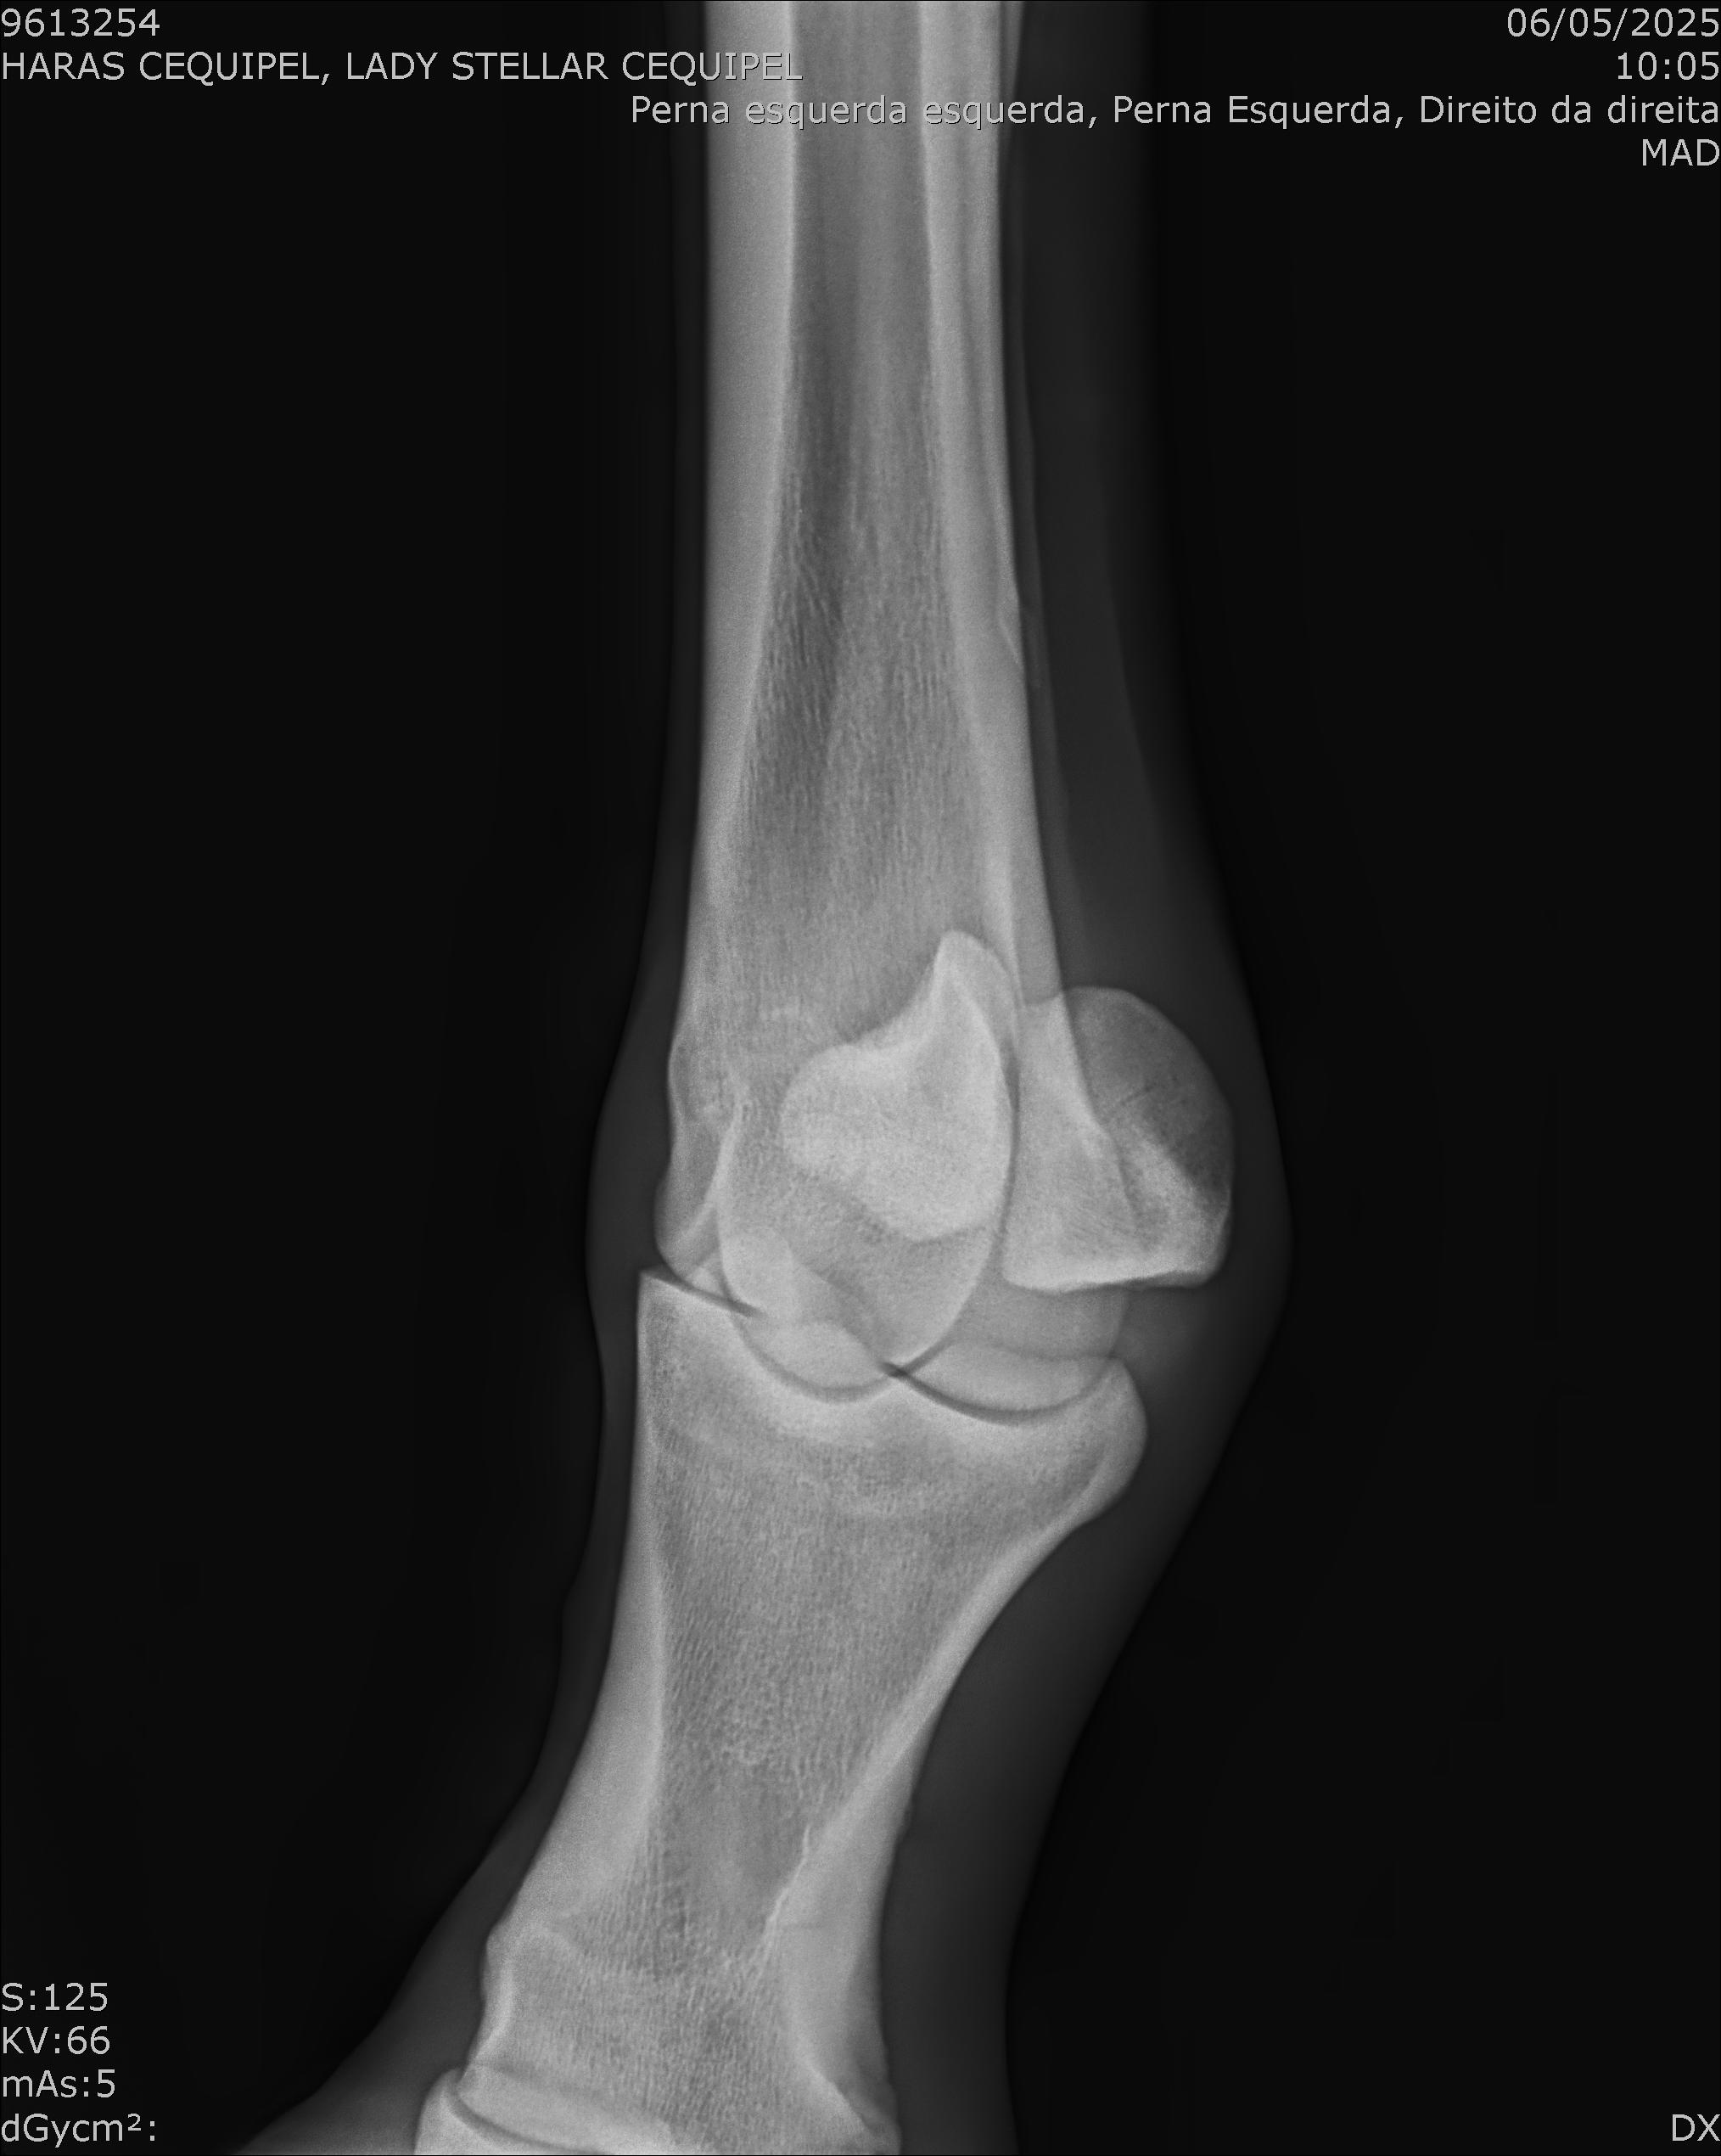

:: RAIOS-X DO LOTE